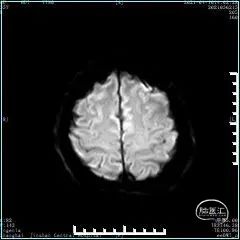

术前影像学检查

头颅MRI:未见明显脑梗死灶。

MRI-SWI未见微出血。